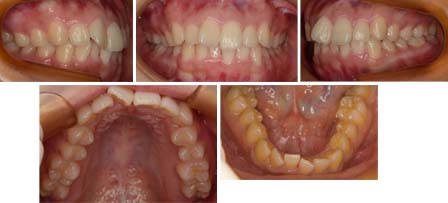

来院時の写真

気になっている点(主訴): 出っ歯

上顎中切歯が捻じれて外に飛び出しています。下顎前歯にも叢生があります。排列するのに必要な量えお計測して、口もとが前方に飛び出ないか?で非抜歯、リンガルブラケットで治療する事にしました。